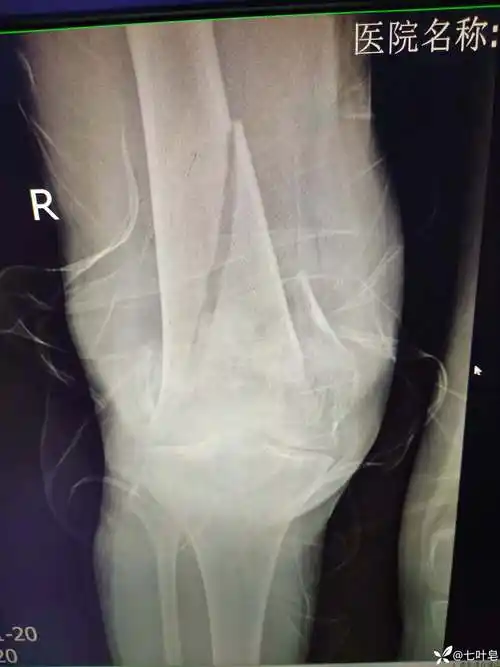

老年股骨髁上髁间骨折分享